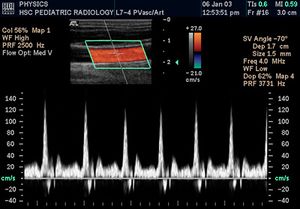

التخطيط الصدى الدوپلري

تكون الصورة عادةً ملونة، فيظهر الدم اما بلون أحمر أوأزرق حسب اتجاه الجريان بالنسبة للمجس الفاحص. ويقدم الجهاز معلومات ممتازة في تقييم صمامات القلب وارتفاع الضغوط الدموية في الأوعية الدموية.

تحليل لسرعة جريان الدم بالأوعية.